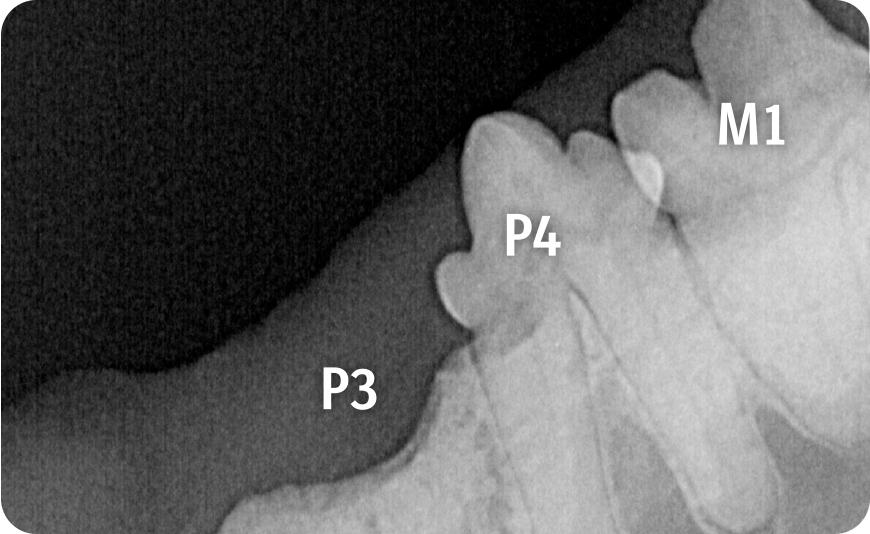

Über entsprechende Röntgenbefunde kann die Zahnresorption aufgezeigt werden. Durch die Visualisierung des Kalenders haben Tierärzt:innen ein gutes Medium, um zu erreichen, dass ihre Botschaft von Tierhalter:innen nicht nur gehört, sondern auch verstanden wird. Wichtig dabei ist die Unterscheidung der einzelnen Typen der Erkrankung. Die intraorale Aufnahme des Unterkiefers rechts zeigt eine Zahnresorption Typ 1 bei M1 mit fokaler Zahnresorption im Kronenbereich sowie den Übergang zur Wurzel bei erhaltenem Parodontalspalt. Bei P3 und P4 werden durch die Aufnahme fehlende Kronenbereiche mit nur noch schwach nachvollziehbaren resorbierten und in Knochengewebe umgebauten Wurzeln erkennbar sowie der Verlust des Parodontolspalts, also eine Zahnresorption vom Typ 2.

Die Bildgebung zeigt, wie unterschiedlich Zahnresorptionen bei der Katze im Röntgen aussehen können. Wichtig für die Praxis zu wissen ist, dass sie je nach Typ unterschiedlich behandelt werden müssen: So ist eine Kronenamputation nur bei einer Typ-2-Zahnresorption mit vollständigem Verlust des Parodontalspalts möglich. Bei Zahnresorption Typ 1, also bei einem erhaltenen Parodontalspalt, müssen alle Wurzeln extrahiert werden.